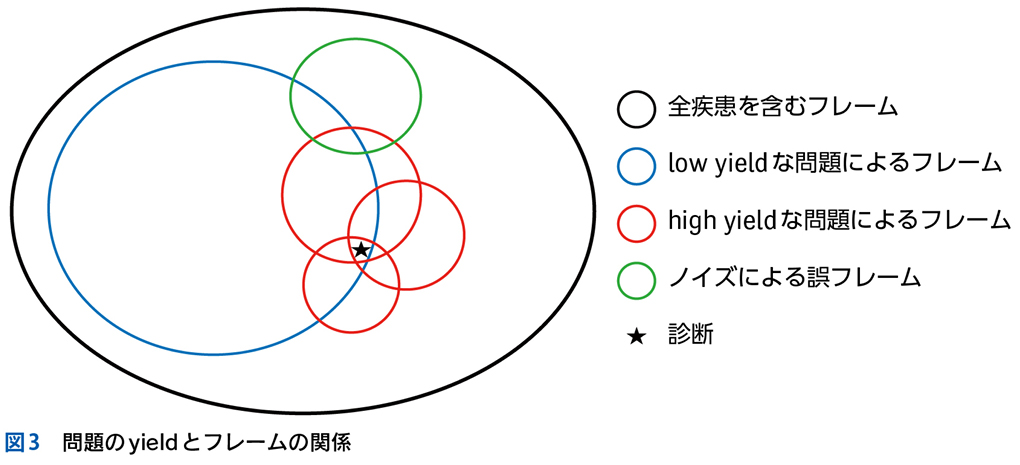

▶ フレームの広さを決めるのは,定義された問題の“yield”である。yieldとは「産み出す」というような意味で,定義された問題がどれほど診断に資するかによって,問題のyieldが高い(high yield),低い(low yield)という使い方をする。high yieldな問題によるフレームは狭く,可能な診断の数を大きく絞り,診断をぐっと近づける。言い換えれば,ある診断(の一群)に対して特異度が高い。一方で,low yieldな問題によるフレームは広く,鑑別診断を意味のある数に絞ることに役立たない(図3)。

▶ 症例によっては,ここまで述べたような条件を満たす問題を複数定義できることがある。この場合は,それぞれの問題が描くフレームが重なり合うところに診断があると考えるとよい(図3)。